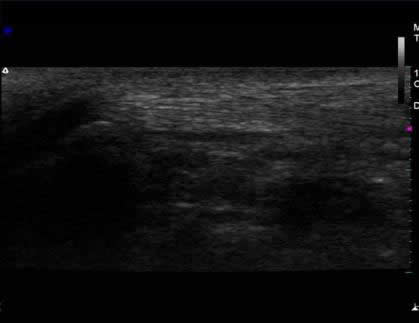

2) Ultrasonografía musculoesquelética de control:

Fotos 2 A y B. Imágenes de corte longitudinal articulación del codo. (A) Se observa bolsa sinovial con menor contenido hipoecogénico, delimitada por bandas hiperecogénicas más delgadas.

(B) Obsérvese mayor detalle